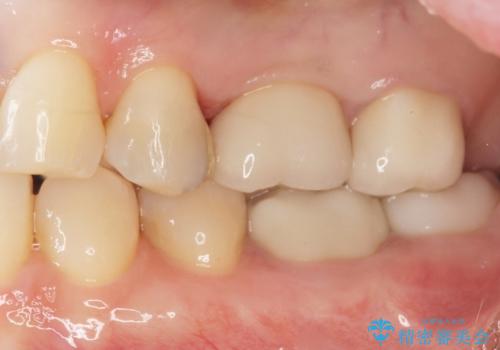

治療後はしみなくなり、違和感のない自然な咬み心地にご満足頂けました。

「割れる心配のないゴールドにしたいけれど、目立ってしまうかしら...」と心配されており、不要に歯質を削合しないよう注意を払い最小限の大きさのインレーを装着したところ、「あまり目立たなくて良かった!」とおっしゃって下さいました。

審美面でセラミックに劣りますが、奥歯の治療には最適な材料です。